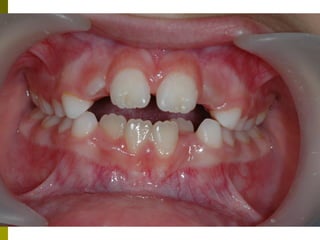

Πρώτη σχολική ηλικία 6-10 ετών

   Αρχίζει αλλαγή των τομέων και η ανατολή των

πρώτων μόνιμων γομφίων (μεικτή οδοντοφυΐα)

   Παρατηρούμε η αλλαγή δοντιών να γίνεται με τη

σωστή σειρά και στη σωστή θέση

   Μπορεί να χρειαστεί πρώιμη ορθοδοντική

θεραπεία, για να αποφευχθούν πιο δύσκολες και

πολύπλοκες εργασίες αργότερα

   Διατήρηση νεογιλών δοντιών στον οδοντικό

φραγμό μέχρι τη φυσιολογική τους απόπτωση